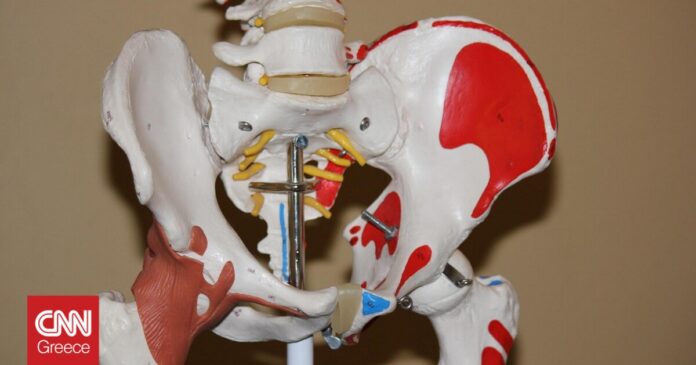

Οι γυναίκες που κάνουν φυτοφαγική διατροφή, έχουν 33% μεγαλύτερο κίνδυνο να πάθουν κάταγμα στο ισχίο (γοφό), σε σχέση με όσες τρώνε κρέας τακτικά (τουλάχιστον πέντε φορές την εβδομάδα), όπως προκύπτει από μια νέα βρετανική επιστημονική έρευνα.

Αφού ελήφθησαν υπ’ όψιν άλλοι παράγοντες όπως το κάπνισμα, βρέθηκε ότι οι φυτοφάγες γυναίκες ήταν η ομάδα με τον πιο αυξημένο κίνδυνο για το εν λόγω κάταγμα. Οι επιστήμονες τόνισαν την ανάγκη το ζήτημα να μελετηθεί περαιτέρω, ώστε να εξηγηθούν καλύτερα οι ακριβείς αιτίες που η φυτοφαγική διατροφή σχετίζεται με αυξημένο κίνδυνο κατάγματος του ισχίου.

«Η μελέτη μας δεν αποτελεί προειδοποίηση προς τους ανθρώπους να εγκαταλείψουν τις φυτοφαγικές διατροφικές συνήθειές τους. Οι φυτοφαγικές δίαιτες μπορεί να διαφέρουν σημαντικά από άνθρωπο σε άνθρωπο και να είναι υγιεινές ή ανθυγιεινές, όπως συμβαίνει και με τις δίαιτες που περιλαμβάνουν ζωικά προϊόντα. Είναι πάντως ανησυχητικό ότι οι φυτοφαγικές δίαιτες συχνά έχουν χαμηλότερα θρεπτικά συστατικά που συνδέονται με την υγεία των οστών και των μυών. Τέτοιες θρεπτικές ουσίες, όπως η πρωτεΐνη, το ασβέστιο κ.α., είναι γενικά πιο άφθονες στο κρέας και στα άλλα ζωικά προϊόντα από ό,τι στα φυτά. Η χαμηλή λήψη τέτοιων ουσιών μπορεί να οδηγήσει σε μικρότερη οστική πυκνότητα και χαμηλότερη μυϊκή μάζα, κάτι που καθιστά κάποιον πιο ευάλωτο στον κίνδυνο κατάγματος στο ισχίο», δήλωσε ο Γουέμπστερ.

Η μελέτη βρήκε ότι ο μέσος δείκτης μάζας σώματος είναι ελαφρώς μικρότερος στους φυτοφάγους από ό,τι στους κρεατοφάγους. Προηγούμενη μελέτη έχει συσχετίσει τον χαμηλό δείκτη μάζας σώματος με αυξημένο κίνδυνο για κάταγμα του ισχίου. Οι λιποβαρείς άνθρωποι έχουν γενικά χειρότερη οστική και μυική υγεία, συνεπώς αν είναι και φυτοφάγοι, ο κίνδυνος κατάγματος είναι μεγαλύτερος. Υπό διερεύνηση είναι κατά πόσο τα ευρήματα της μελέτης ισχύουν εξίσου για τους άνδρες.